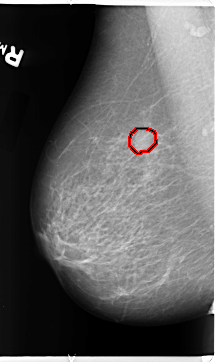

B_3113_1.RIGHT_MLO

RIGHT_MLO LINES 4696 PIXELS_PER_LINE 2792 BITS_PER_PIXEL 12 RESOLUTION 50 OVERLAY

FILE: B_3113_1.RIGHT_MLO.OVERLAY

TOTAL_ABNORMALITIES 1

ABNORMALITY 1

LESION_TYPE MASS SHAPE ROUND MARGINS CIRCUMSCRIBED-ILL_DEFINED

ASSESSMENT 4

SUBTLETY 4

PATHOLOGY BENIGN

TOTAL_OUTLINES 1

BOUNDARY